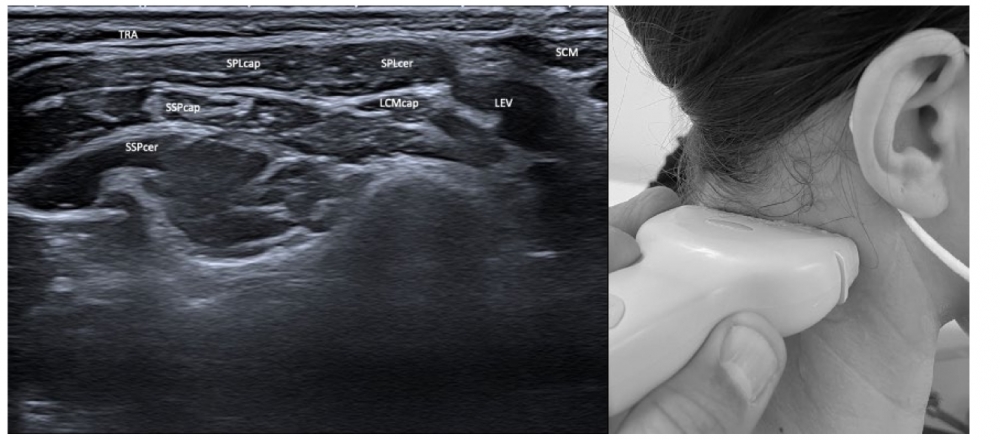

ULTRASOUND OF CERVICAL DYSTONIA Superficial Layers: TRA: Trapezius

Deep Layers SCM: Sternocleidomastoid CV1 & 2: Atlas and axis vertebrae

|

LATERAL

POSTERIOR Superficial

Intermediate

Deep